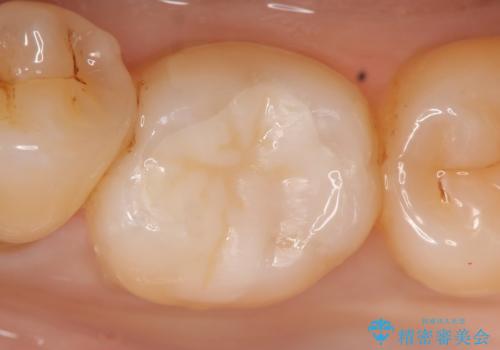

セラミックインレー 虫歯で欠けた歯の治療